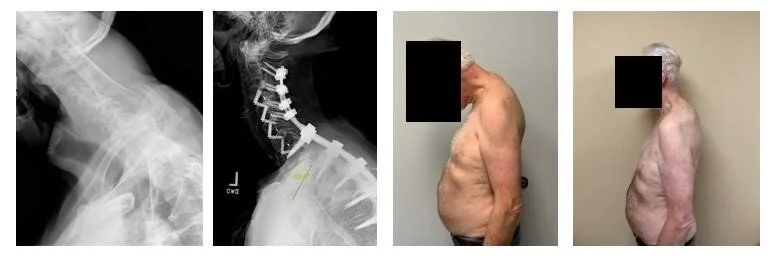

In this case, Dr. Chase Bennett, Spine Surgeon, Novant Health Brain and Spine Surgery—Kimel Park, performs a multi-staged thoracic pedicle subtraction osteotomy and spinal fusion using Coroent Small Interlock, Vuepoint 2, Reline, Bendini OCT and NuVasive Power to correct hyper kyphosis and restore lordosis in a patient suffering from ankylosing spondylitis.

• Diagnosis: Ankylosing spondylitis resulting in thoracic hyper kyphosis; loss of cervical lordosis

Dr. Bennett determined that the best course of action to correct the patient’s hyper kyphosis and restore lordosis in the cervical and upper thoracic spine would involve a complex two-stage procedure. The first stage of the procedure involved a C3-C7 ACDF utilizing CoRoent Small Interlock interbody implants to restore sagittal alignment in the cervical spine. This procedure was followed by the second stage which involved a pedicle subtraction osteotomy (PSO) at T1 and posterior fixation from C2-T5 utilizing Bendini, Vuepoint 2, navigation and Reline 3CO.

• Stage 2: T1 PSO; C2-T5 posterior fixation

Dr. Bennett was able to restore a normal gaze and cervical lordosis for the patient through this procedure. The patient was on his feet the next day and began physical therapy within nine days of his procedure. Five months into his recovery, he is at or ahead of schedule, expecting to return to normal activity within a year.